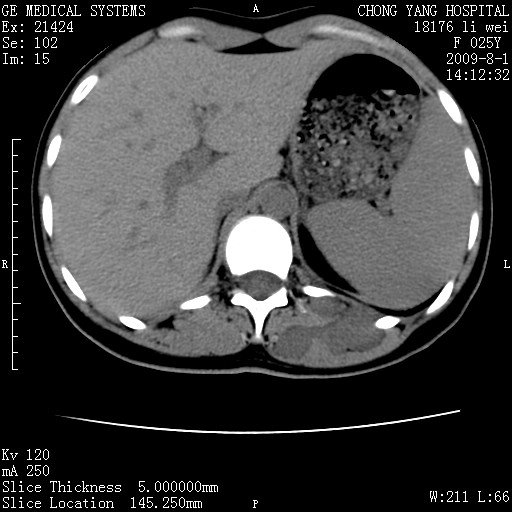

以下是引用pujunzhi在2009-8-1 20:23:00的发言:[br]胸椎旁及背部肌间良性病变,范围广,边界清,沿肌间生长,考虑淋巴管瘤、血管瘤,建议增强扫描。

以下是引用拾荒者在2009-12-30 21:45:00的发言:[br]ct21383:神经纤维瘤病( nf) [br] [br] 神经纤维瘤病。四肢都有,影响美观,四肢上的手术了。[br] [br] [br]谢谢!